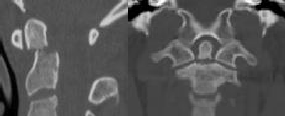

Figures 1 through 3 show the radiograph and CT images of a 68-year-old

woman who sustained a cervical injury after tripping over her cat. She has mild facial trauma, which includes a broken upper incisor and a nonsurgical nasal fracture. She is neurologically intact. Her past medical history is consistent with obstructive sleep apnea, non–insulin-dependent diabetes mellitus (hemoglobin A1c level of 9.0), and morbid obesity, with a body mass index of 40. What is the preferred treatment for this patient?

4. Anterior odontoid screw fixation Discussion: C

Posterior C1-2 fusion with instrumentation provides stability and pain relief with excellent clinical outcomes despite the loss of C1-2 motion. Hard collar immobilization and halo vest immobilization both carry a substantial risk of nonunion in this patient because of her age, fracture displacement, residual fracture gap, and medical condition. Anterior odontoid screw fixation theoretically preserves C1-2 motion. In this case, the fracture is not reduced. Concentric reduction is a requisite for osteosynthesis of the odontoid. Her body habitus also may not allow anterior odontoid fixation.